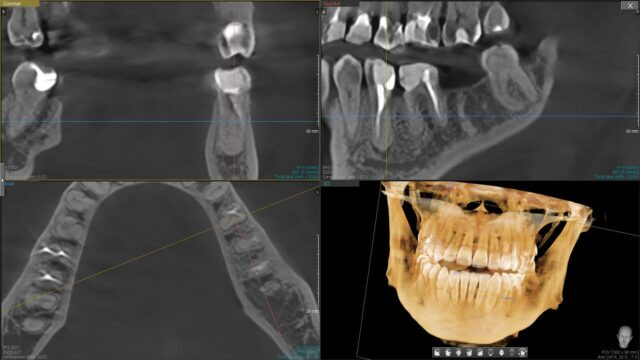

Tomografia CBCT 3D pozwala dokładnie ocenić wysokość i szerokość wyrostka, jakość kości (gęstość), położenie struktur krytycznych (kanał nerwu zębodołowego dolnego, zatoka szczękowa, otwór bródkowy) oraz tor planowanego wszczepu. Dzięki temu chirurg unika niespodzianek śródzabiegowych, a protetyk projektuje śrubowy lub cementowy tor pracy zgodny z przyszłą koroną/mostem.

„Dobre CBCT = dobry plan. Najpierw bezpieczne pozycjonowanie i przewidywalny tor protetyczny, potem implantacja. To skraca czas leczenia i minimalizuje ryzyko powikłań.”